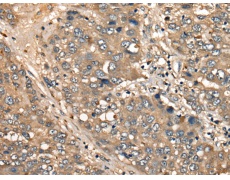

IHC positive control: |

Human liver cancer |